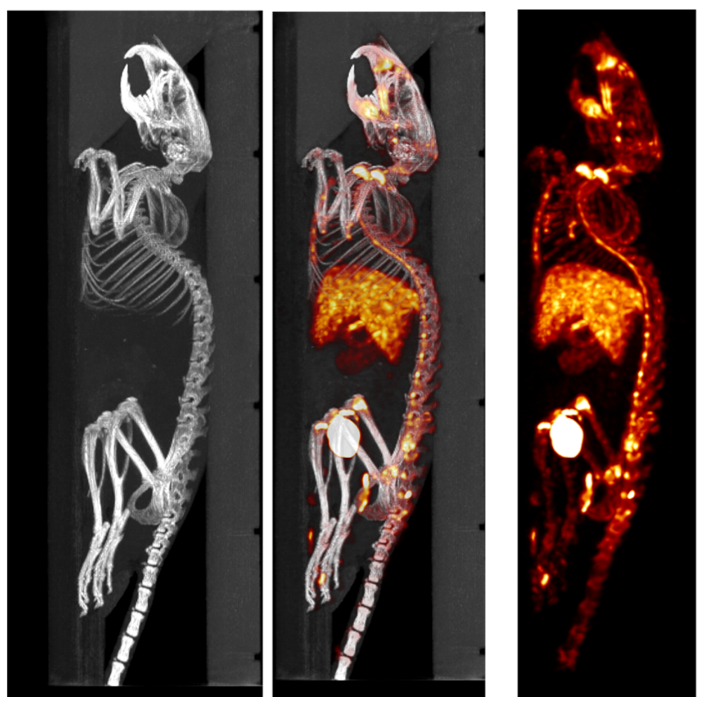

1、神經(jīng)系統(tǒng)SPECT成像

大鼠腦部SPECT成像:99mTc-HMPAO:腦血流灌注顯像劑,用于腦血管疾病,腦外傷,癲癇,癡呆癥,腦死亡的診斷;用于精神疾病的腦功能及正常腦生理功能活動(dòng)的研究。進(jìn)入腦組織的99mTc-HMPAO構(gòu)型改變而轉(zhuǎn)變成水溶性化合物,無法再次通過血腦屏障而滯留在細(xì)胞內(nèi),因此能在腦內(nèi)長(zhǎng)時(shí)間滯留。120 MBq,30 min uptake,30 min SPECT。

神經(jīng)系統(tǒng)成像.jpg